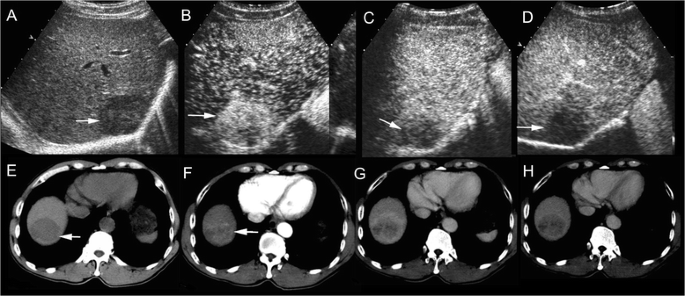

cHCC-CC in a patient with chronic hepatitis B. Simultaneous elevation of AFP (718 ng/ml) and CA19-9 (45.0U/ml) was detected in the patient. Unenhanced ultrasound shows a hypoechoic mass of 4.6 cm in right lobe of the liver (a, arrow). The mass displays heterogeneous hyperenhancement in the arterial phase (b, 26 s after contrast agent injection) followed by quick (c, 58 s after injection) and marked washout (d, 102 s after injection) in the portal phase on CEUS, resembling the enhancement pattern of intrahepatic cholangiocarcinoma. Unenhanced CT scan reveals a hypodense mass in right lobe of the liver (e, arrow). The mass displays heterogeneous hyperenhancemen in the arterial phase (f, arrow) followed by washout (g) in the portal phase and the late phase (h) on contrast-enhanced CT, resembling the enhancement pattern of HCC